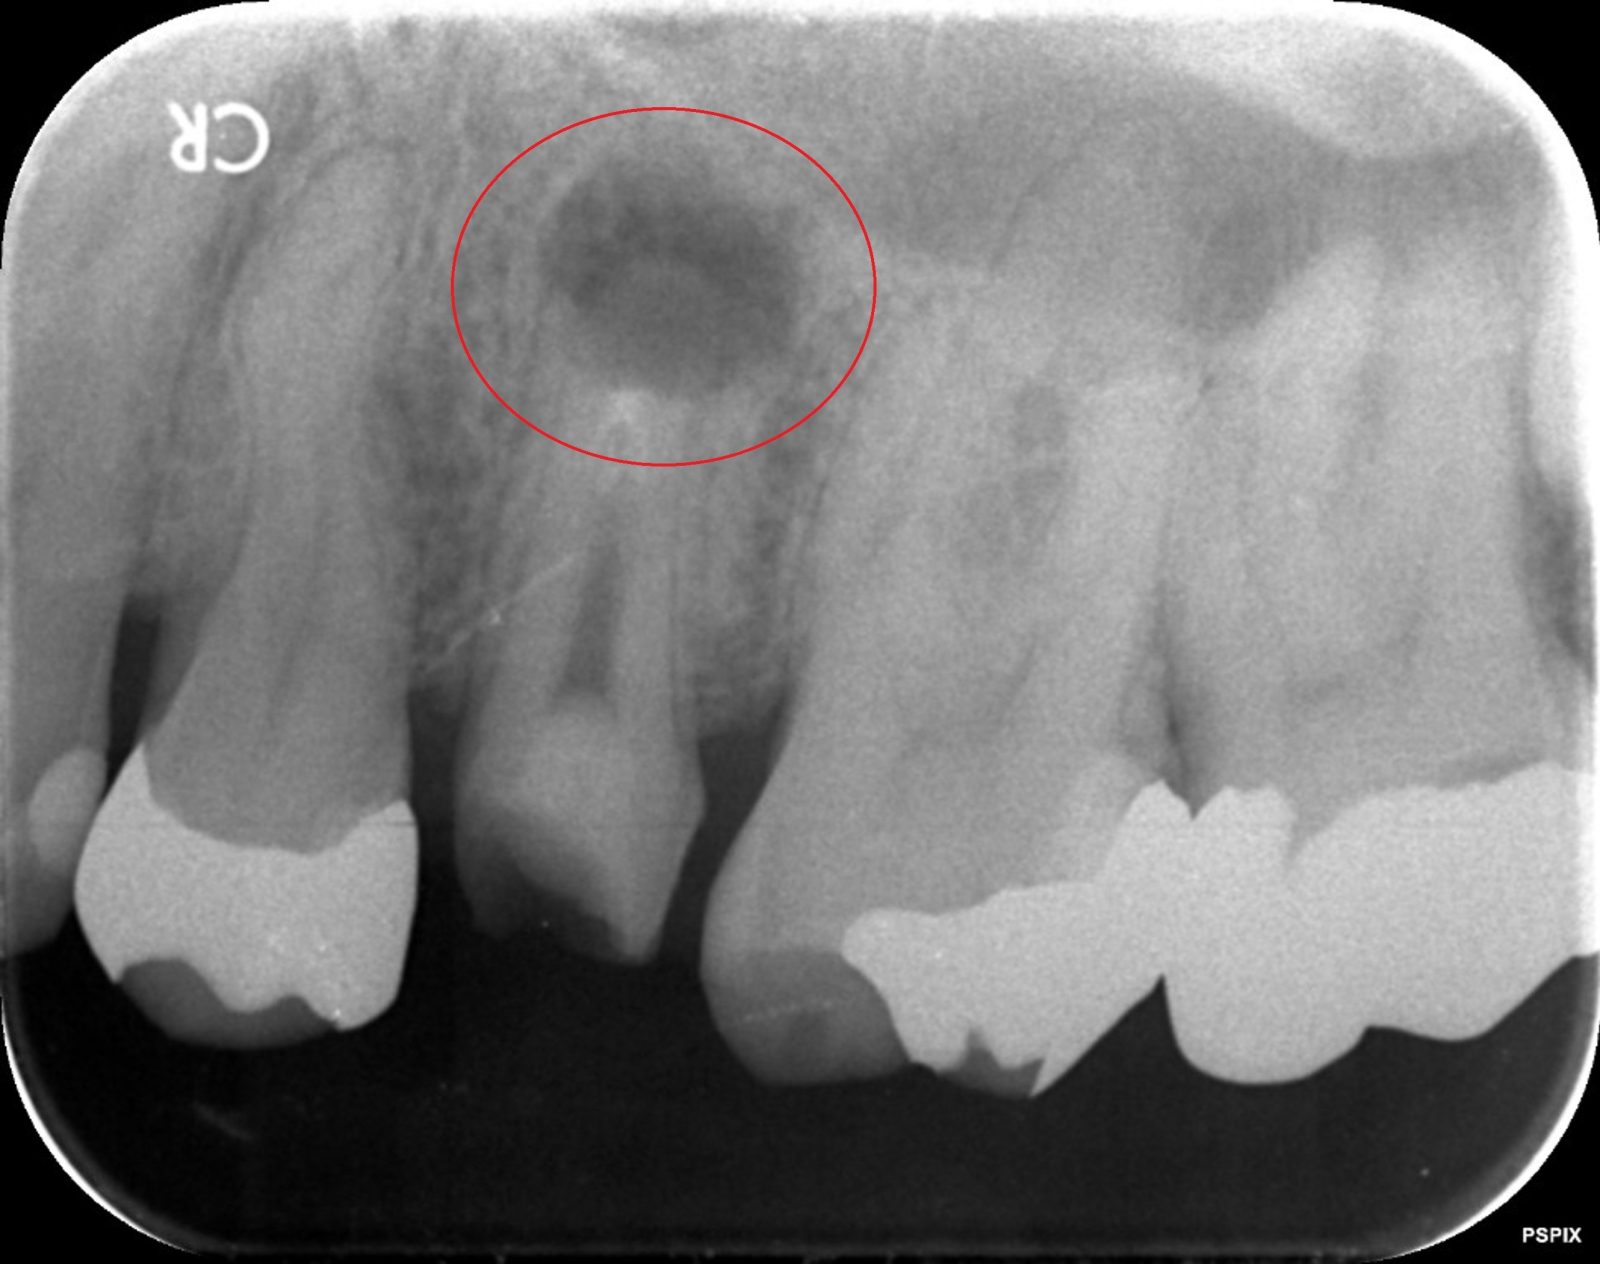

次の画像は、同じ患部をCTとレントゲンで撮影した画像です。

• 比較

「左」の写真がCTで、「右」の画像がレントゲンで撮影したものです。

赤丸で囲んだところには、黒い影が見えます。ここには炎症が起こっているのですが、右の写真には影がありません。つまり、2次元のレントゲンだけで診断した場合、問題のある部分は治療しない選択をするため、最終的には抜歯の運命をたどるケースです。